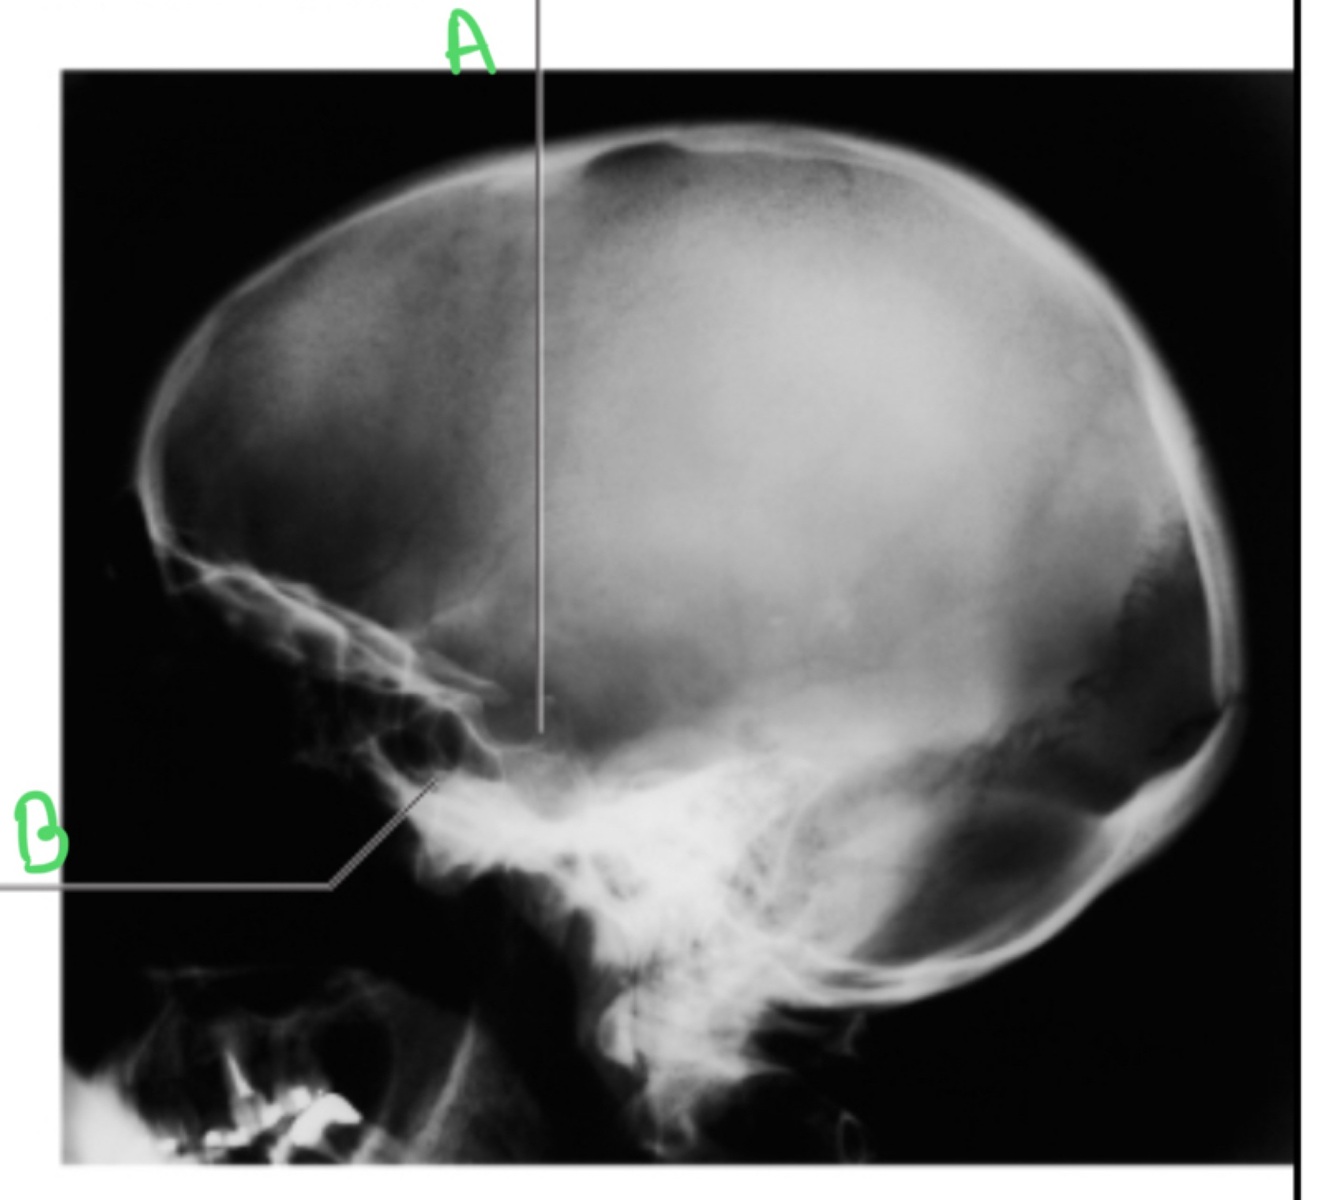

A = hypophyseal fossa

B = sphenoid sinus